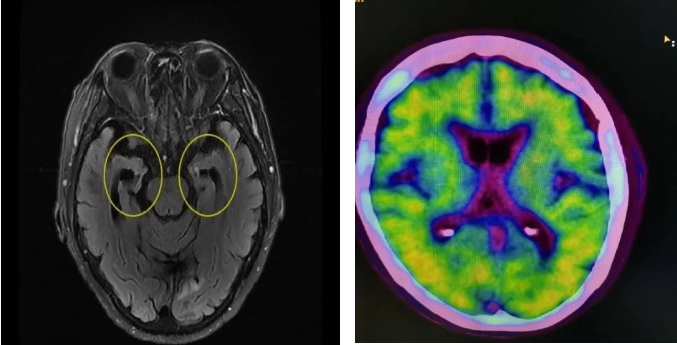

西南脑科专家介绍说

阿尔茨海默病不是“老糊涂”,家人正在被疾病悄然吞噬,亲人却往往忽略了早期征兆,无数患者因此错过最佳诊疗时机。许多被耽误的阿尔茨海默病患者来问诊时,病情已经发展到中重度。患者自己痛苦的同时,也给家属们带来极其沉重的经济心理双重压力。